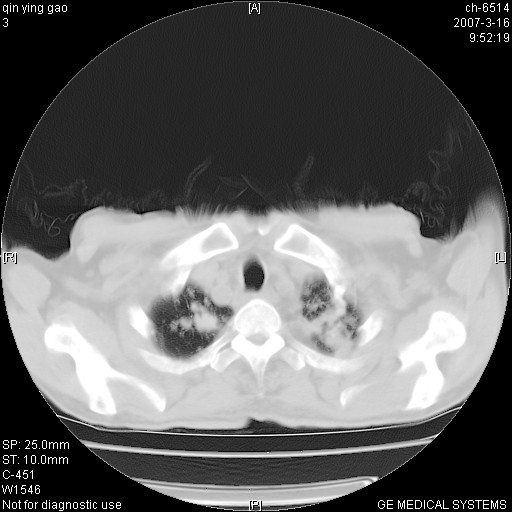

男,64岁.乏力2个月,畏寒、发热1月余。体重下降。血沉加快,白细胞不高。

双肺以中上肺野为著斑片状.结节壮密度增高影 左上肺前段可见小类圆钙化灶 纵隔淋巴结无明显肿大

双肺以中上肺野为著斑片状.结节壮密度增高影,纵隔淋巴结无明显肿大。考虑:

男,64岁.乏力2个月,畏寒、发热1月余。体重下降。血沉加快,白细胞不高。 双肺可见大小不等结节状密度增高影,密度不均,分布不均(双肺上叶为著),亚急性血行播散性肺结核.